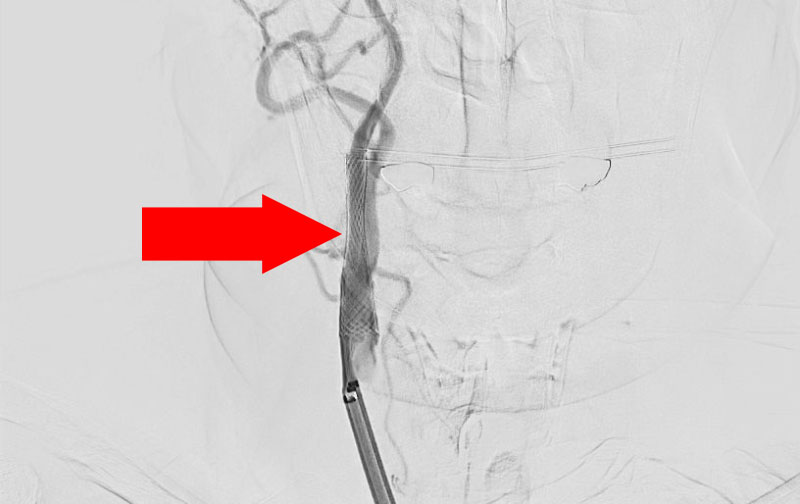

No.1270 手術中

左内頚動脈脳動脈瘤

50代

大阪府の病院